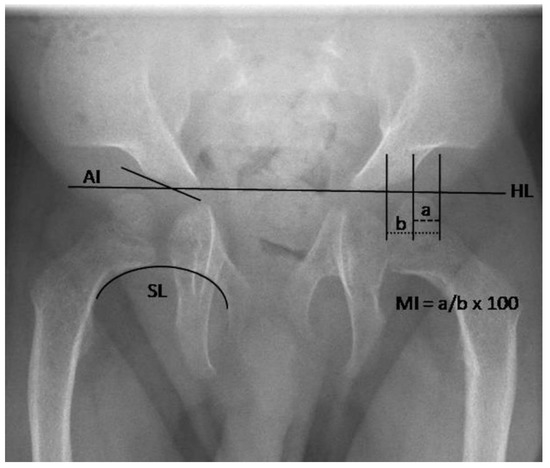

3.2.2. Quantitative Assessment of Radiographs